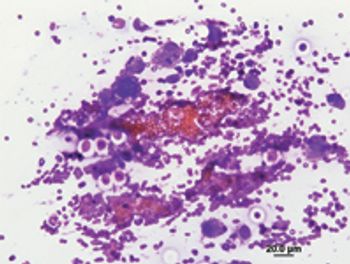

Salivary mucoceles are formed by the extravasation and accumulation of saliva in tissues adjacent to a salivary gland. The accumulated saliva incites an inflammatory response, leading to a walled-off accumulation of mucoid fluid.